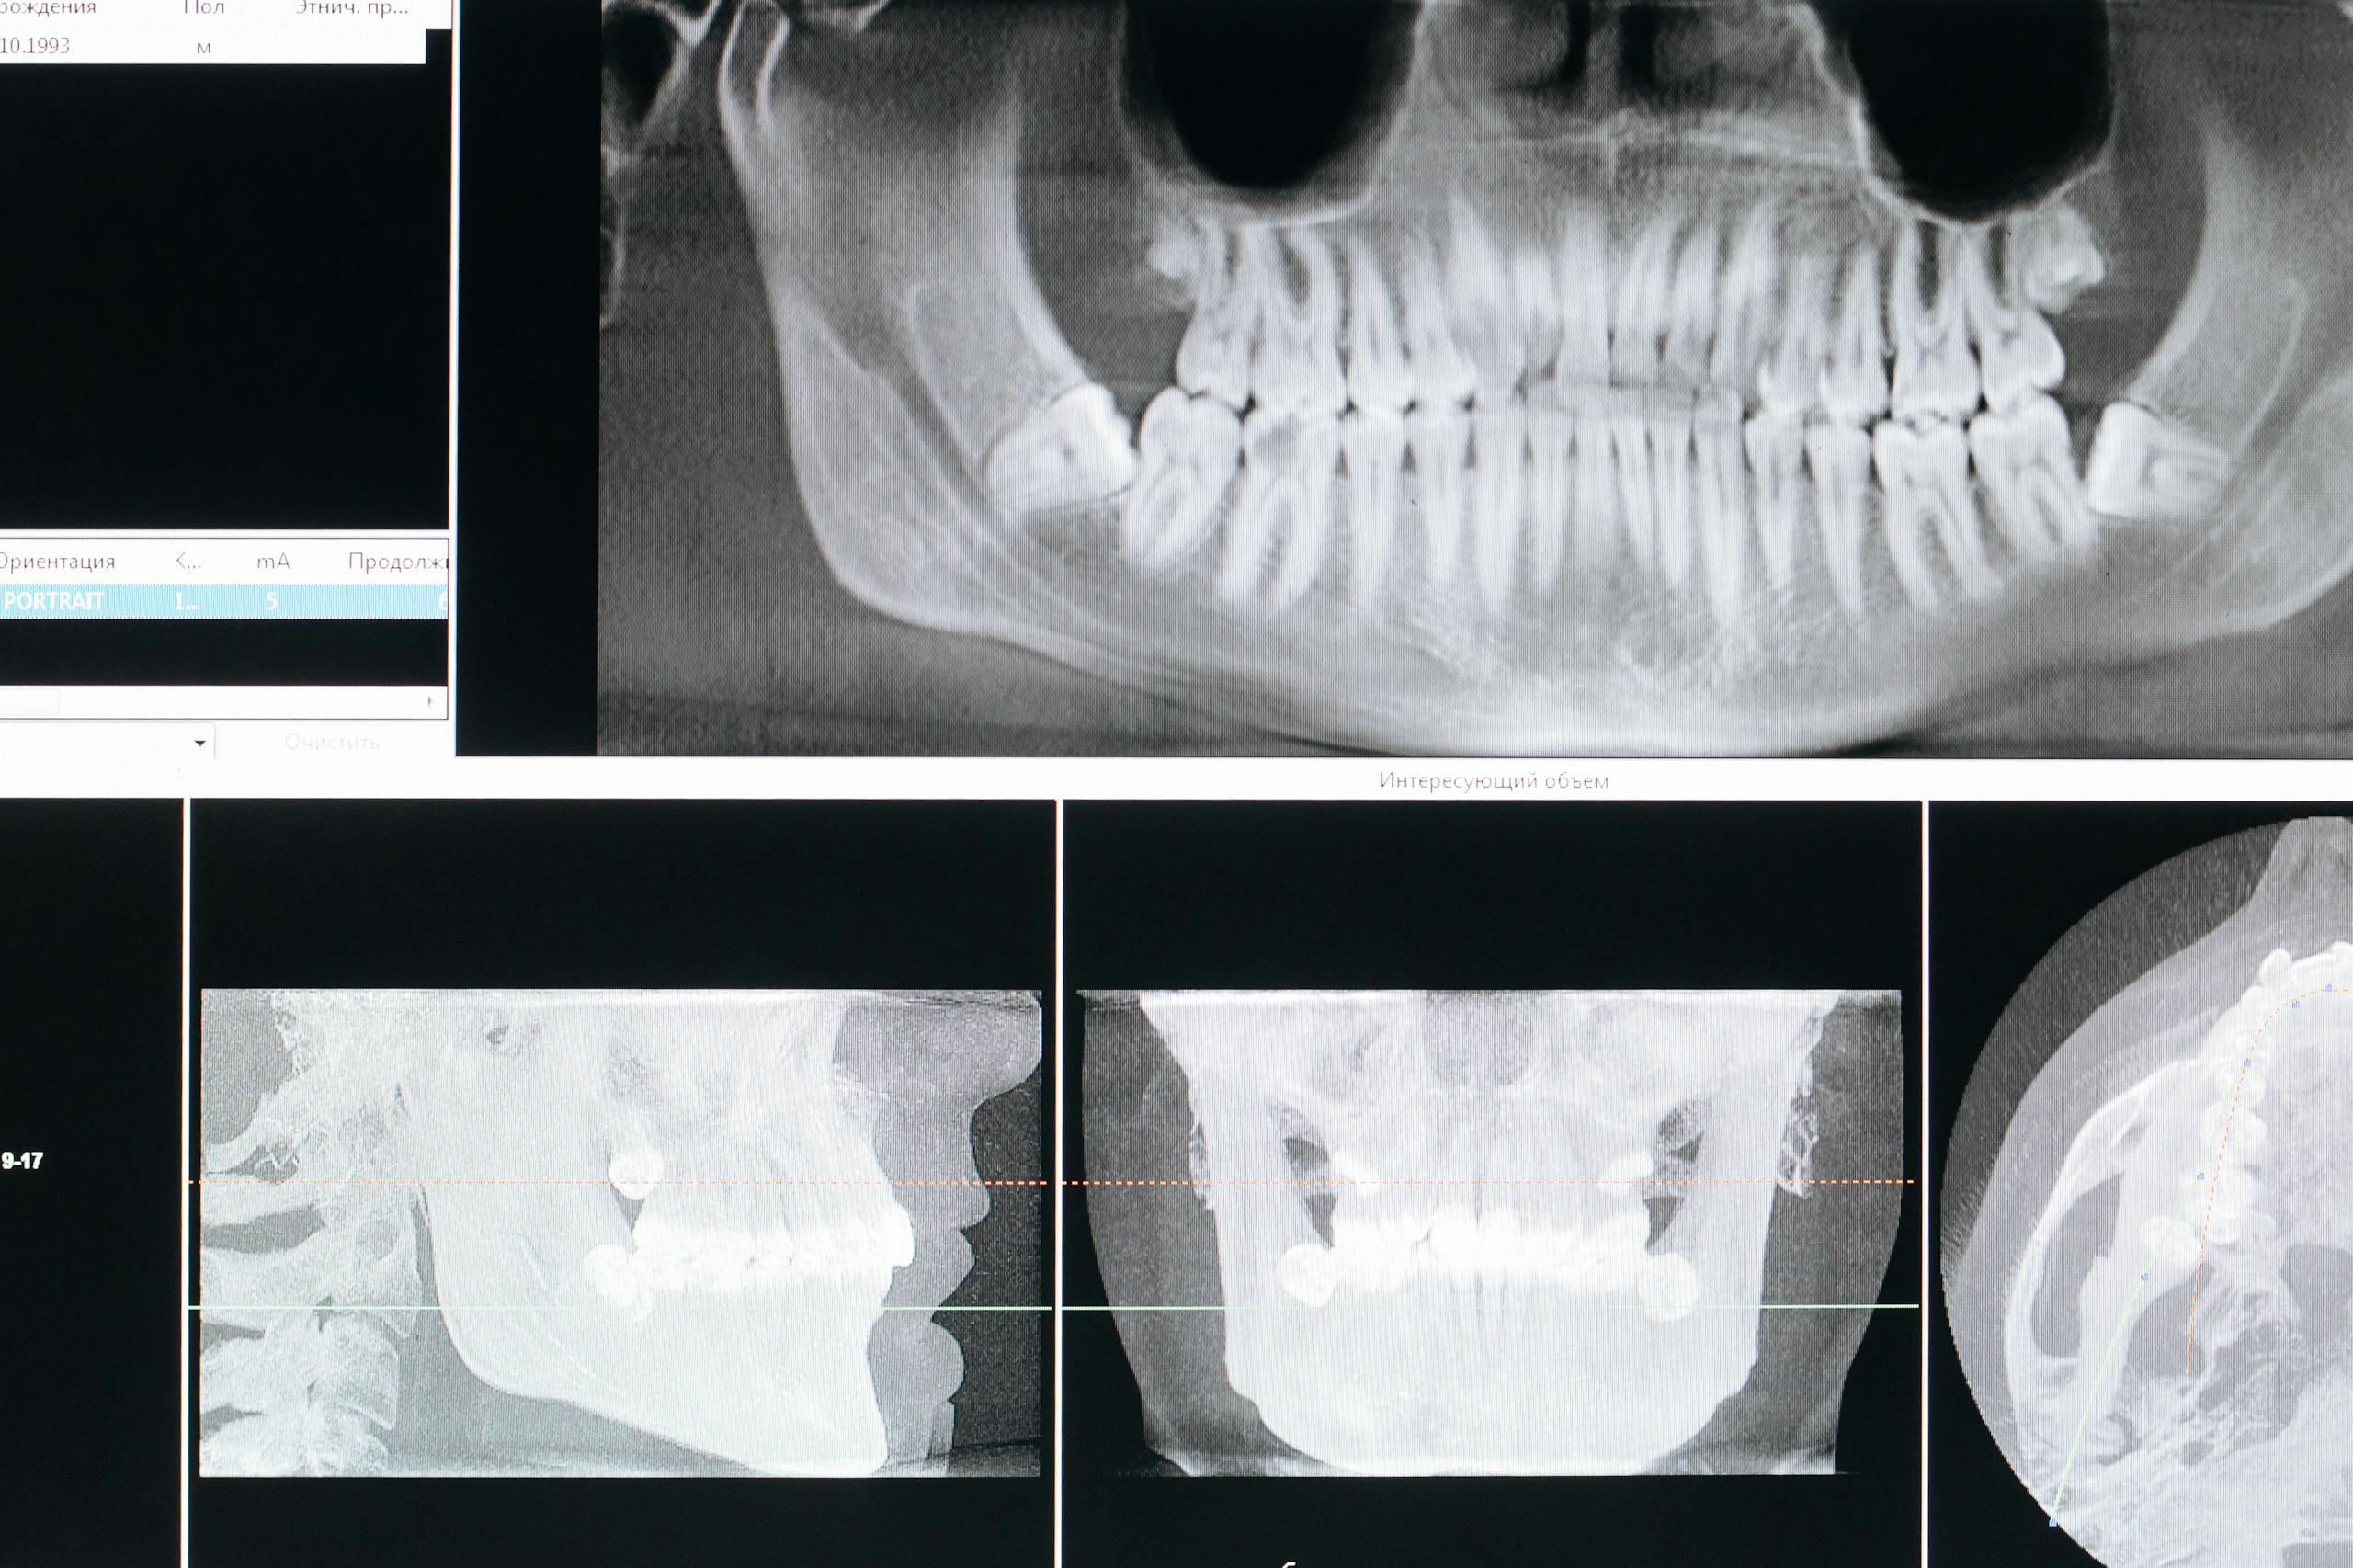

CBCT is a 3D dental scan. It can show teeth, roots, bone, nerves, sinuses, and nearby anatomy in more detail than a standard 2D dental X-ray. The important question, however, is not whether 3D imaging is newer. It is whether the scan is likely to answer a specific clinical question that could change diagnosis, safety, or treatment planning.

A CBCT scan creates a 3D view of a limited area of the mouth or jaws. Depending on the reason for the scan, that added detail may help a dentist or specialist assess:

- the height and width of bone

- the position and shape of roots

- the relationship between teeth and nerves

- the location of the sinus floor

- complex anatomy that may not be obvious on 2D images

- some bone defects or surgical landmarks